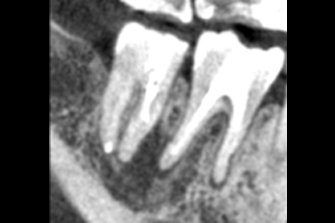

多発性歯根嚢胞を精密根管治療、歯根端切除術を行なった症例

治療後

| 治療内容 | ラバーダム、マイクロスコープ、 MTAを用いた精密根管治療 歯根端切除術 |